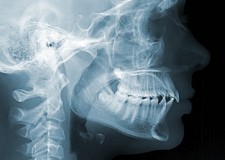

L’Unità Operativa di Radiologia Odontoiatrica, ubicata presso il Dipartimento, è dotata di apparecchiature all’avanguardia nella diagnostica odontostomatologica e del massiccio-facciale. In particolare è presente un’apparecchiatura TC Cone Beam di ultima generazione che consente l’acquisizione volumetrica ad alta definizione ed a bassissima dose dell’intero volume cranio-facciale comprese le articolazioni temporo- mandibolari e le prime vertebre cervicali. Tale esame oggi trova larga applicazione nel campo della diagnostica odontoiatrica e del massiccio facciale, come lo studio pre e post-implantare, la valutazione di elementi dentali inclusi, lo studio di lesioni odontogene e non odontogene, la traumatologia cranio-facciale ed anche la valutazione dei seni paranasali, dell’orecchio e delle articolazioni temporo-mandibolari. Grazie all’acquisizione volumetrica ed alla bassa dose di radiazioni tale metodica è oggi indicata anche nella pianificazione del trattamento ortodontico. Nell’Unità Operativa è inoltre presente l’Orthophos Plus della Sirona Dental System che consente di effettuare esami radiografici standard digitali delle arcate dentarie, dei seni paranasali e delle articolazioni temporomandibolari ed inoltre teleradiografie nelle proiezioni latero-laterale ed antero-posteriore per studio ortodontico. L’Unità Operativa è collegata in rete con i vari reparti della clinica per una rapida consultazione degli esami radiologici.